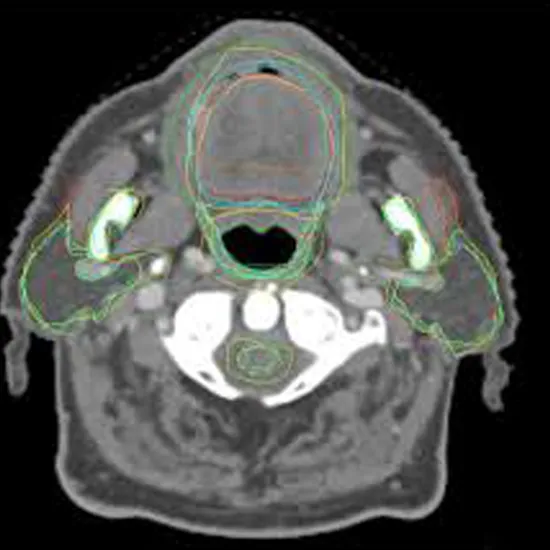

CT Neck with oral cavity is an imaging procedure used to diagnose and detect problems in the neck region and oral cavity. This scan gives clear information about the aneurysms, tumors, infections, thyroid nodules, other disorders in the neck region, the presence of a tumor, and lymph nodes in the oral cavity.

CT neck with oral cavity is a non-contrast-based study. This scan helps your doctor to visualize the internal structure of the neck and oral cavity region to establish the diagnosis of pertaining conditions and diseases.